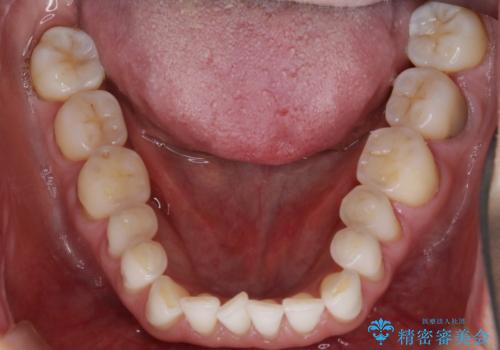

【非抜歯】マウスピースでオープンバイトを治す

- 歯ぎしりや食いしばり、噛み合わせの治療とガタつきを治したいとのことでご来院されました。

検査の結果、前歯と臼歯の高さに差があり、前歯が全く当たらない状態になっているため歯ぎしりによって奥歯が削れてしまっているという状態でした。

マウスピースの矯正装置を用い、ガタつきを治しつつ奥歯を沈めていくことで噛み合わせ全体の改善を図りました。